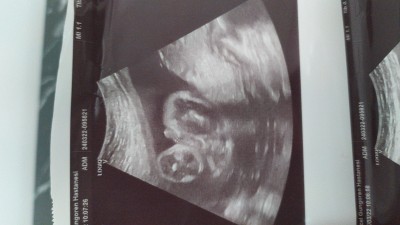

Hanımlar 25.haftadayım daha hala cinsiyeti göremedik.. Doktor hep saklıyor dedi bacaklarını birbirine geçiriyor.. Bugun yalnizca böyle birşey yakaladık doktor da emin olamadı ama kordonu mu pipisi mi diye Sizce erkek mi?

Gebelik haftası 25